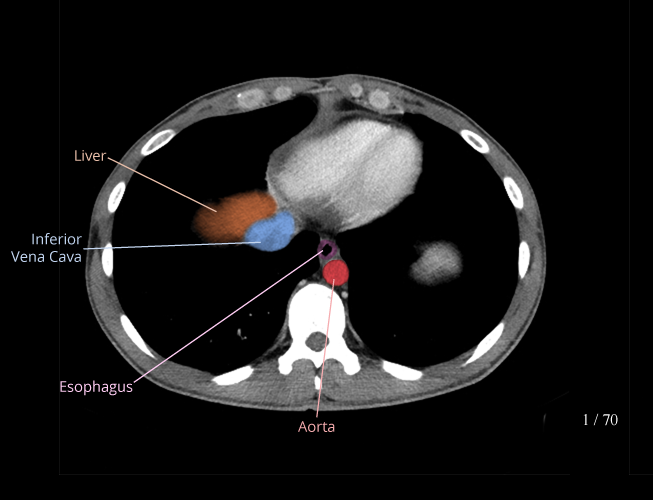

Chest

Covers basic chest radiograph and chest CT anatomy.